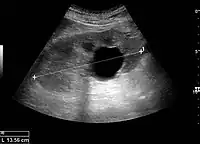

Figure 1. Normal adult kidney. Measurement of kidney length on the US image is illustrated by ‘+’ and a dashed line. *Column of Bertin; ** pyramid; *** cortex; **** sinus.[1]

The length of the adult kidney is normally 10–12 cm, and the right kidney is often slightly longer than the left kidney. The adult kidney size is variable due to the correlation with body height and age; however, normograms for pediatric kidney size are available.[1]

Cortical thickness should be estimated from the base of the pyramid and is generally 7–10 mm. If the pyramids are difficult to differentiate, the parenchymal thickness can be measured instead and should be 15–20 mm (Figure 3). The echogenicity of the cortex decreases with age and is less echogenic than or equal to the liver and spleen at the same depth in individuals older than six months. In neonates and children up to six months of age, the cortex is more echogenic than the liver and spleen when compared at the same depth.[1]